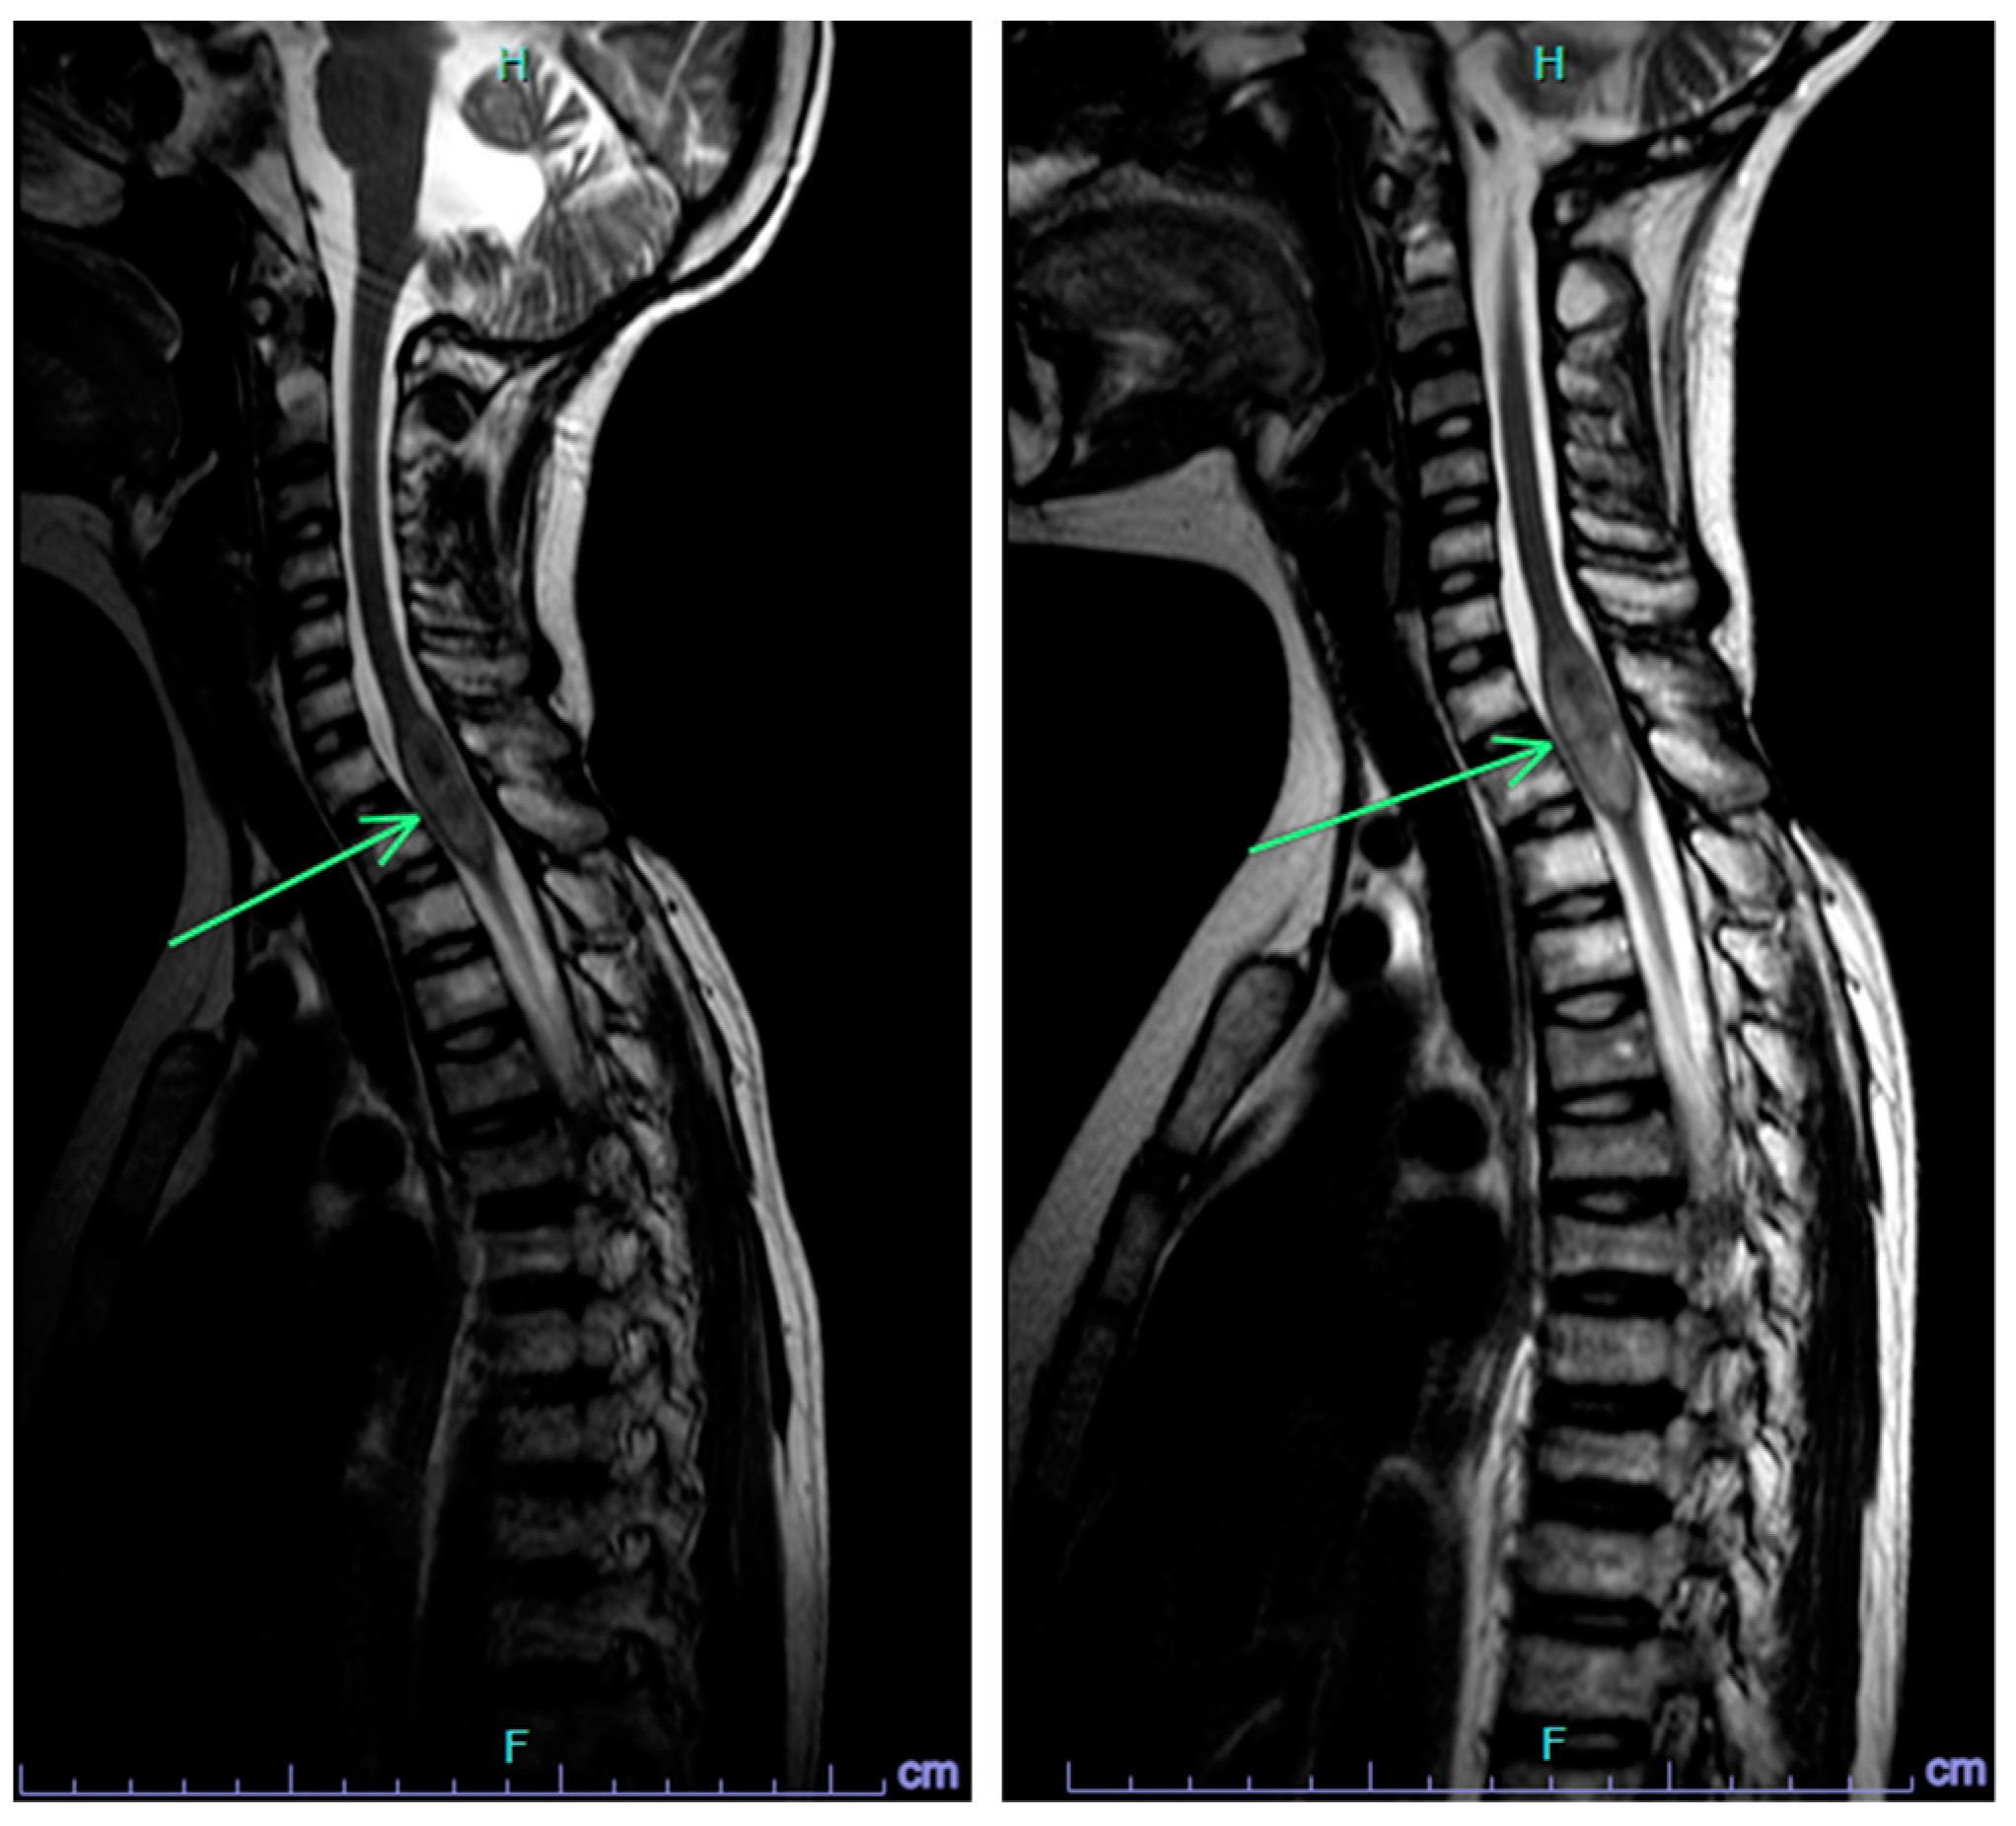

2.1. Case 1